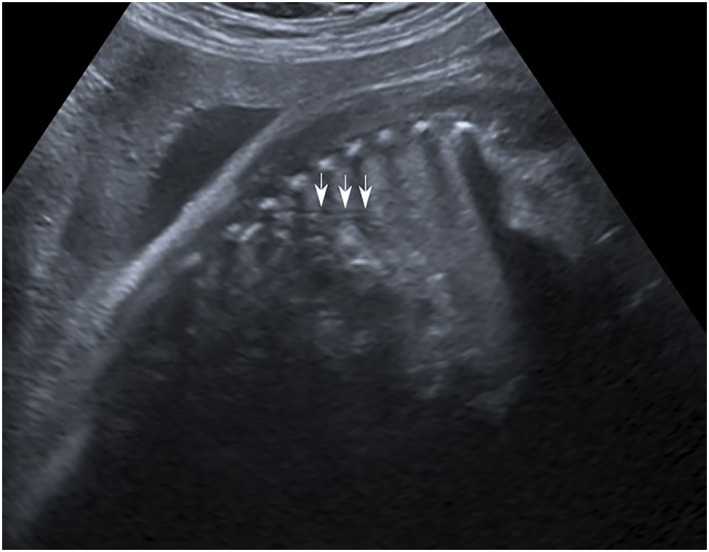

Results: One case was diagnosed by magnetic resonance imaging (MRI) and two by ultrasound with MRI confirmation. Two patients were referred to our center for diaphragmatic hernia (with a sac in one case). The third patient was referred because of a thoracic aorta on the very left side. After birth, costal anomalies, agenesis of the body and tail of the pancreas, and an associated pelvic kidney were diagnosed. All neonates were presented with acute respiratory distress; two had a favorable outcome, and the third died within the first few days of life.